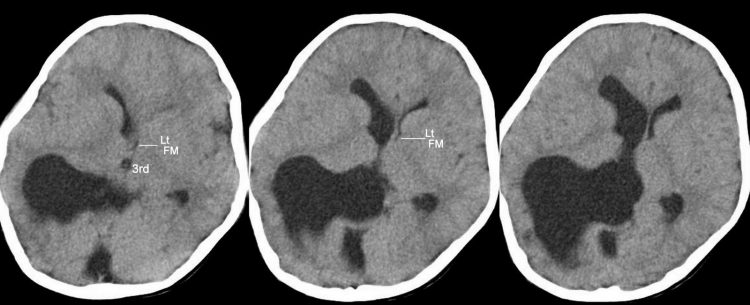

Εάν η αξονική ή μαγνητική τομογραφία δείξουν διάταση των κοιλιών του εγκεφάλου, δηλαδή πιθανή υδροκεφαλία, ο ασθενής χρήζει αξιολόγησης από εξειδικευμένο νευροχειρουργό.